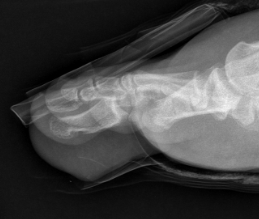

Great toe MTPJ dislocation

Pathology

Hyperdorsiflexion

Metatarsal head dislocates plantar

- tear of plantar plate / disruption bipartite sesamoid

- may buttonhole through capsule / plantar plate